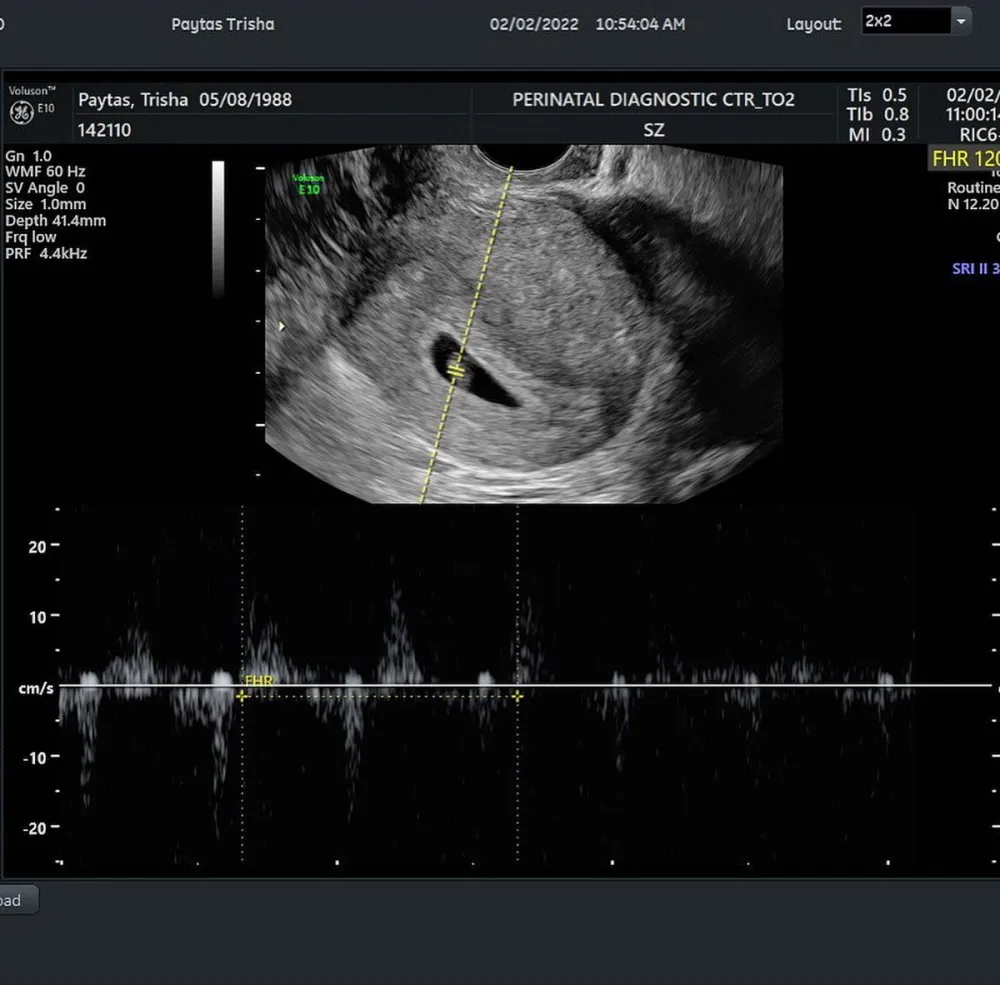

“Love at first [heart]beat. #happyvalentinesday,” the California native, 33, captioned an Instagram video from an ultrasound appointment.

The singer’s husband, Moses Hacmon, shared the news in an Instagram post of his own, writing, “Mom and Dad. Best #valentine gift ever!” In the social media upload, the architect, 44, and his partner grinned while holding a sonogram shot.